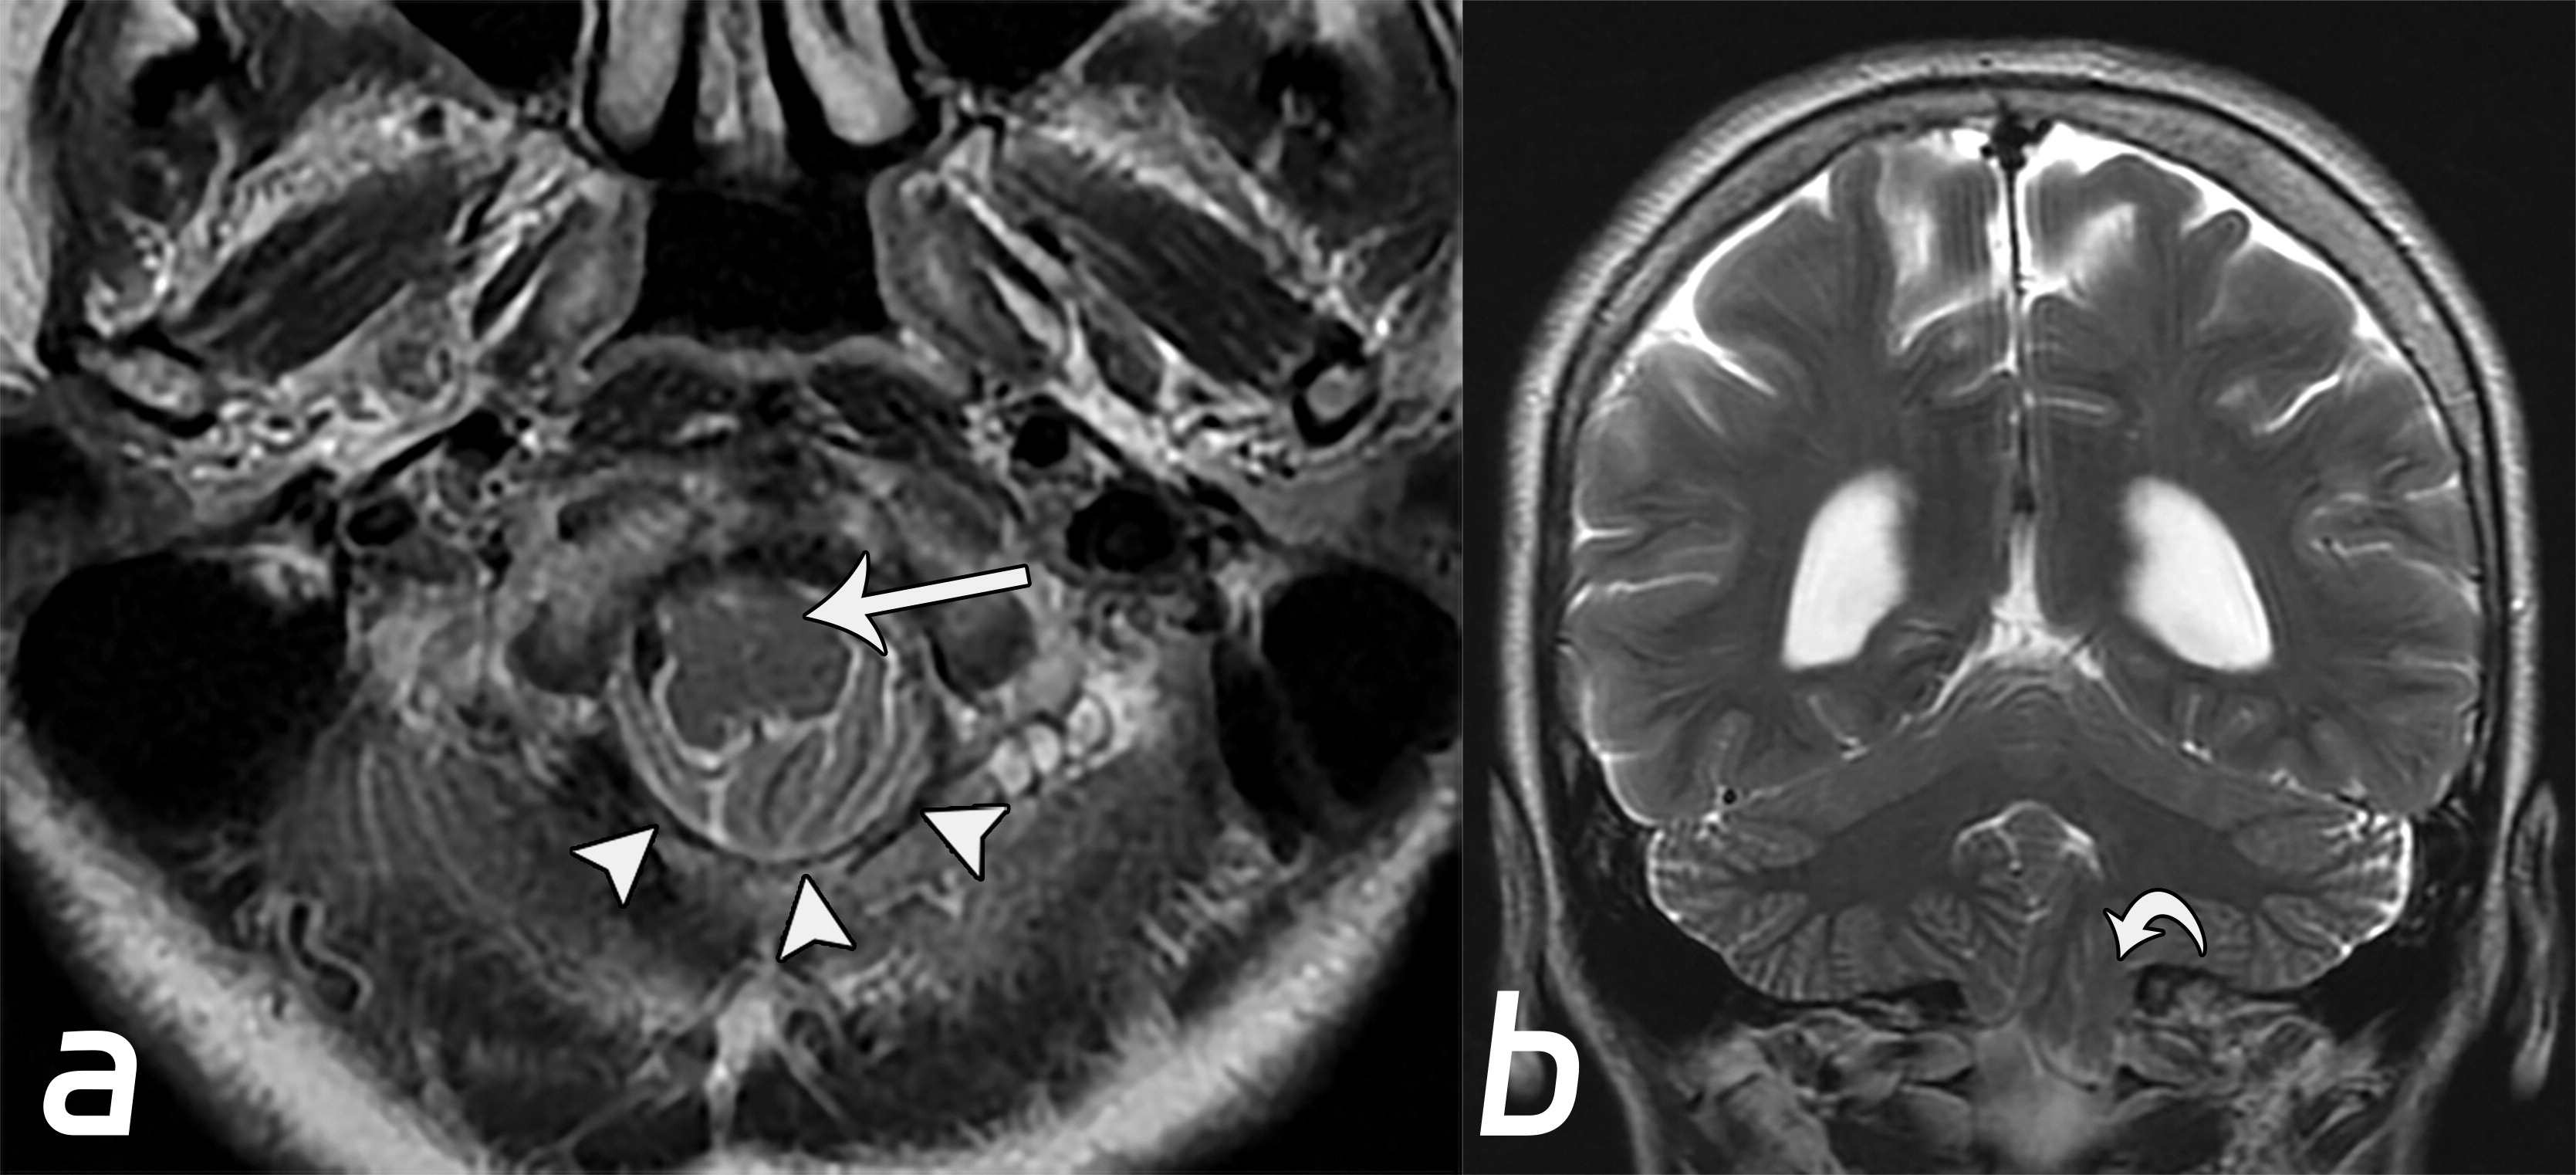

ada0d28046f51452ac0893532b2d281e.jpg

Chiari畸形Ⅰ型。小脑扁桃体下降(b图中白色弯曲箭头),伴脑干向前移位(a图白色长箭头),以及枕骨大孔脑脊液的闭塞(a图中白色短箭头)。

2dc5adc084ecd71c0855dbcfaf191767.jpg

小脑扁桃体疝的示意图。(a图)小脑扁桃体延伸至枕骨大孔的下方(白色弯曲箭头),脑干挤压斜坡(白色长箭头),延髓池的闭塞(黑色长箭头),梗阻性脑积水(黑色*)。(b图)枕骨大孔层面的轴位图,移位的小脑扁桃体(黑色*)导致周围脑脊液的闭塞,延髓向前移位(白色弯曲箭头),挤压脊髓动脉(黑色短箭头)及椎体动脉(白色短箭头)。